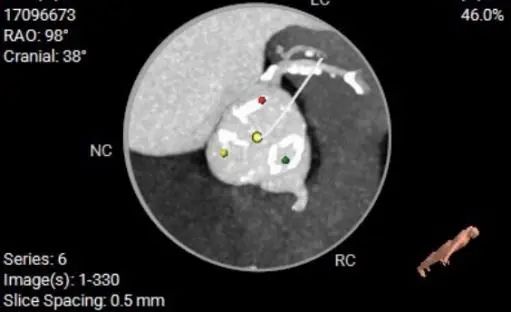

CT数据显示该患者为三叶瓣主动脉瓣。

主动脉瓣瓣环周长65.0mm,平均周长径 20.5mm,sov:25.7mm*27.1mm,瓣叶增厚,钙化主要分布于瓣叶,瓣环水平夹角51°。

冠脉高度测量

LEFT CORONARY

左冠开口高度10.6mm

RIGHT CORONARY

右冠开口高12.0mm

患者三叶式主动脉瓣。瓣叶纤维增厚,轻度钙化。钙化主要分布于瓣叶。右冠高度低,瓣叶长度可,窦宽相对瓣膜小,左冠瓣叶较长,建议20mm球囊球扩评估冠脉风险。

计划使用20球囊预扩张,vitaflow tav24瓣膜进行释放,结合流出道形态及瓣上多平面分析,采取零位释放策略。